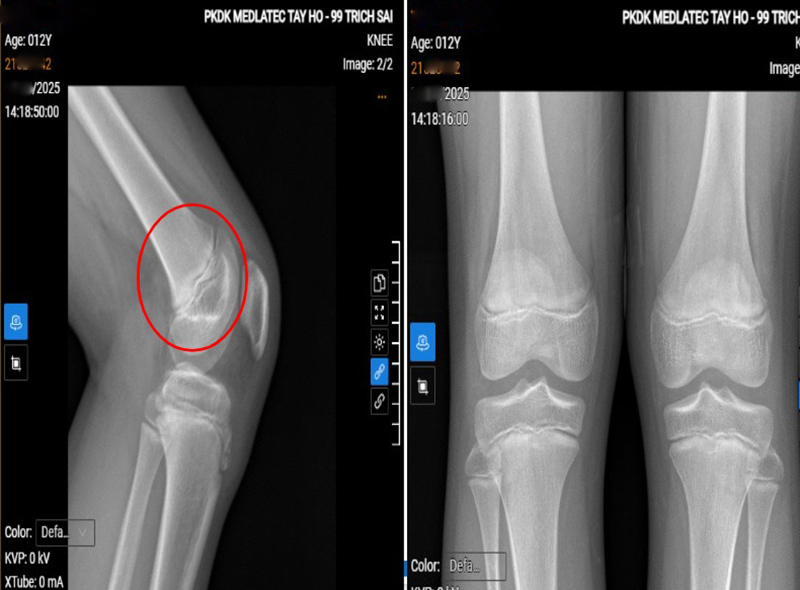

Một bé trai 12 tuổi ở Hà Nội xuất hiện tình trạng đau khớp gối trái tái diễn nhiều ngày sau khi chơi thể thao nên đã đến Phòng khám Đa khoa MEDLATEC Tây Hồ thăm khám. Tại đây, bé được chẩn đoán viêm lồi củ trước xương chày - một bệnh lý phổ biến ở trẻ chơi thể thao, cần phát hiện sớm để tránh ảnh...